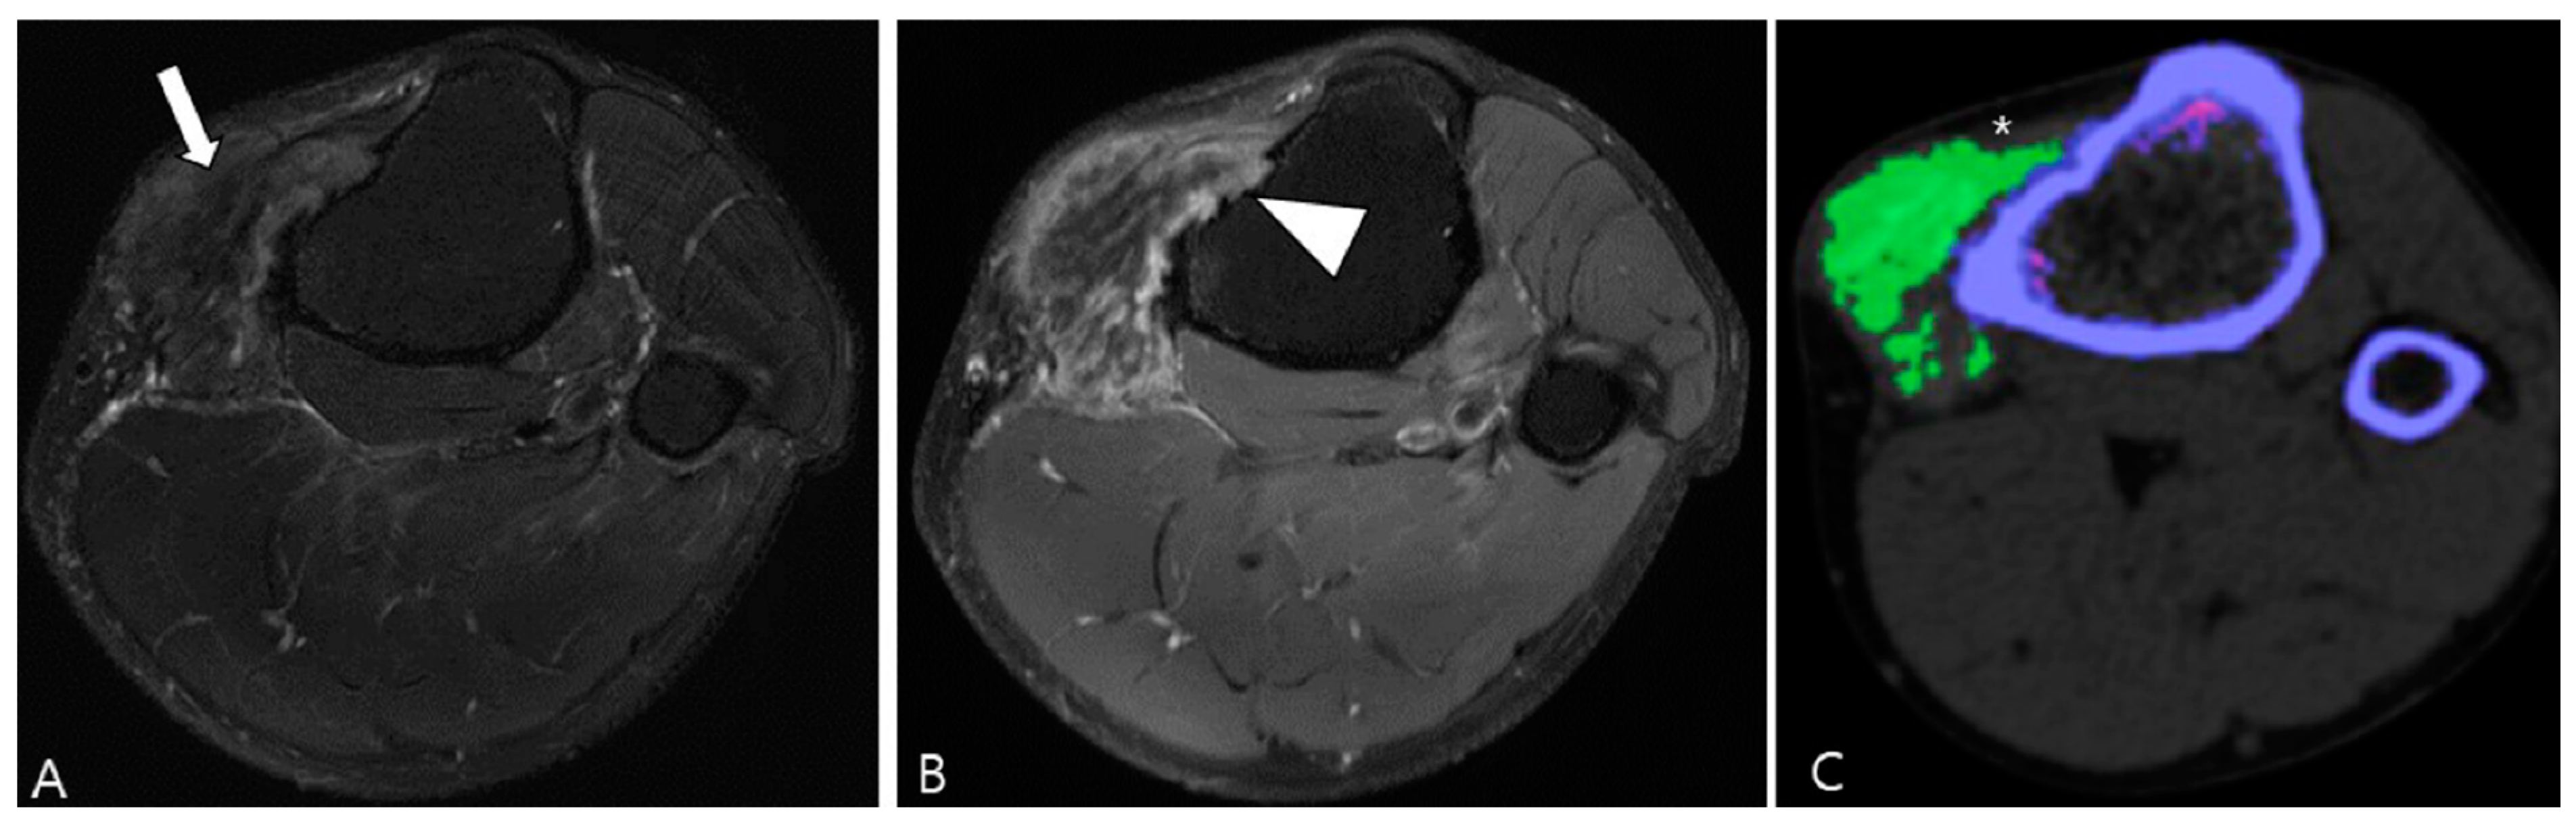

2.5. Advanced MRI Sequences for D-TSGCT

3.2. Differential Diagnoses of Extra-Articular D-TSGCT